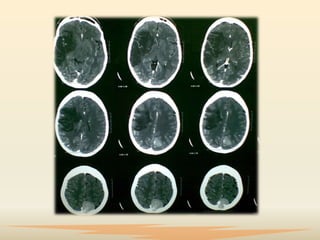

Diagnóstico

 Ante la sospecha deECV, se necesita identificar la lesión y

 La evaluación neuropsicológica de sujetos con daño

producido por ECV está enfocada en conocer las

funciones afectadas y depende del tipo de evento. En

el infarto cerebral se estudia por imágenes radiológicas

los aspectos topográficos de la lesión, especialmente

antes de las 24 horas del inicio del trastorno súbito.

 Los más utilizados son la tomografía computarizada,

la resonancia magnética y el estudio del flujo sanguíneo

regional cerebral.

Diagnóstico  Ante lasospecha deECV, se necesita identificar la lesión y su ubicación y obtener información sobre el estado estructural del parénquima del cerebro y su condición hemodinámica como consecuencia de la lesión.  La evaluación neuropsicológica de sujetos con daño producido por ECV está enfocada en conocer las funciones afectadas y depende del tipo de evento. En el infarto cerebral se estudia por imágenes radiológicas los aspectos topográficos de la lesión, especialmente antes de las 24 horas del inicio del trastorno súbito.

 Los másutilizados son la tomografía computarizada, la resonancia magnética y el estudio del flujo sanguíneo regional cerebral.